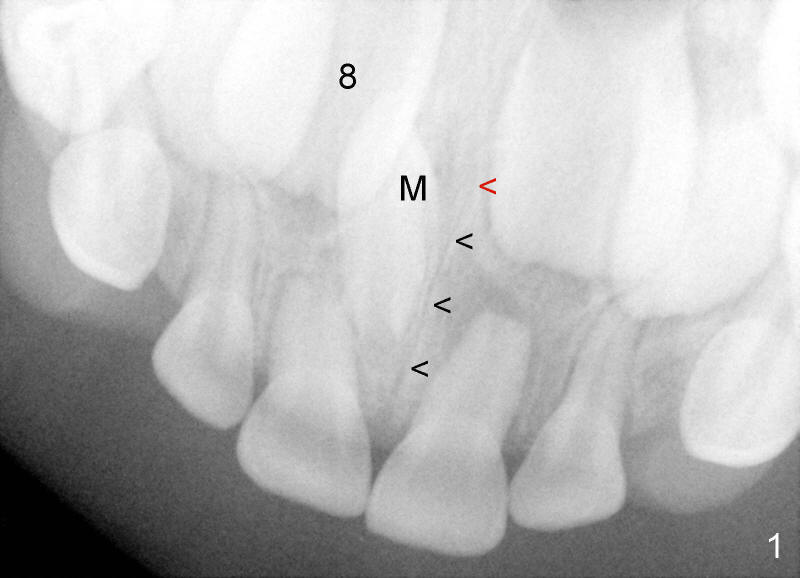

Crown of mesiodens (M) may be oriented toward apically (Fig.1), coronally (Fig.2) or palatally (Fig.4 axial section of CBCT). A common characteristic of mesiodens is that it does not cross midline suture (Fig.1,2 black arrowheads, Fig.4 white arrowheads), although it can push and deform midline suture (Fig.1,2,4 red arrowheads).

CBCT shows that the crown of the mesiodens is palatal (Fig.4: P). Second visual exam of the palate demonstrates an elevation (Fig.3: M) lateroposterior to the incisal papilla (*, a midline structure). It appears that CBCT is not so critical in deciding surgical approach for this case.

There is no problem to expose the mesiodens palatally with mucoperiosteal flap reflection. But the mesiodens is difficult to be luxated after placement of purchase point lateral to the mesiodens (Fig.5 yellow arrowheads). The supranumerary tooth is sectioned (white line). The coronal portion is easy to be removed, but the radical portion is stable (probably ankylosis). Out of desperation, a purchase point (red arrowhead) is placed between the mesiodens and the incisal canal (I). It helps remove the root, but there is oozing after suturing flap. It seems that the neurovascular bundle is violated when the medial purchase point is made.

Although the midline suture and the incisal canal can be pushed to the other side by the expanding mesiodens (Fig.4: red arrowhead and arrow), the mesiodens does not seem to be able to grow across the midline suture.

How does this happen? Here is a hypothesis. Fig.6A diagrammatically shows the developing premaxilla, which consists of the right and left portions, separated by the midline suture (solid arrow) and the incisal canal (I). As well-known, the developing deciduous incisor tooth buds (A, B) give rise palatally to permanent tooth buds (1,2), respectively (open arrows). For unknown reasons, the developing permanent central incisor tooth bud produces medially an extra tooth bud (mesiodens, green circle in Fig. 6B). The cortices of the developing midline suture appears to be a barrier for the developing mesiodens. Unlike deciduous or permanent teeth, the development mesiodens apparently does not have its definitive growth pattern (probably due to its absence of deciduous precursor). It may grow upward (Fig.1), downward (Fig.2) or palatally (Fig.4,6C) along suture cortex.